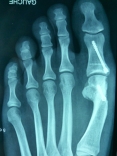

Exemple de correction par une ostéotomie en chevron du pied gauche:

L'INTERVENTION:

translation osseuse de 5mm |

APRÈS: